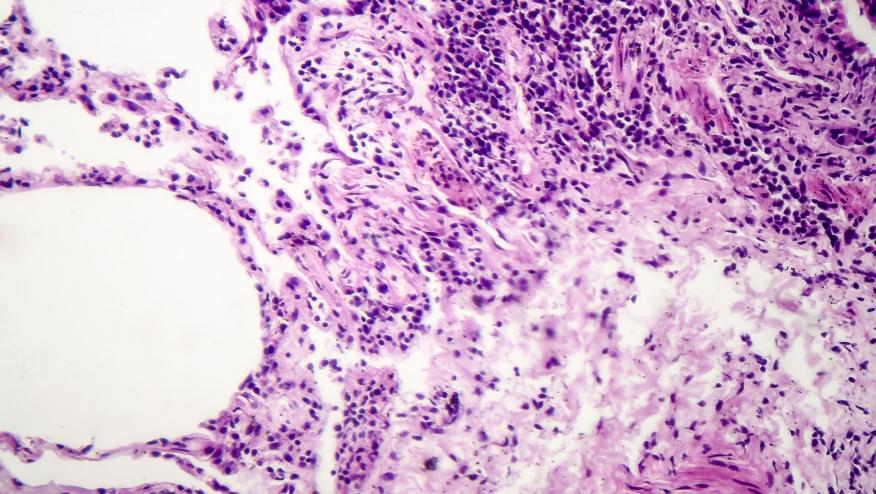

A post hoc, pooled analysis of of rheumatoid arthritis (RA) clinical trials shows those received abatacept had a lower rate of Interstitial lung disease (ILD).

A retrospective analysis of pooled safety data from 10 phase 3 clinical trials of adult RA patients on MTX who were treatd with either ABA or placebo and assess for ILD events (may have included acute respiratory events suggestive of pneumonitis/ILD). Data was drawn from the following trials: AGREE, ATTEST, AIM, ALLOW, ACCOMPANY, ACQUIRE, AVERT, AMPLE, AVERT-2, and early AMPLE. While ILD was not an exclusion criterion for most trials, the AMPLE trial excluded those with severe, progressive, or uncontrolled pulmonary disease. Therefore, some patients may have had pre-existing RA-ILD at baseline.